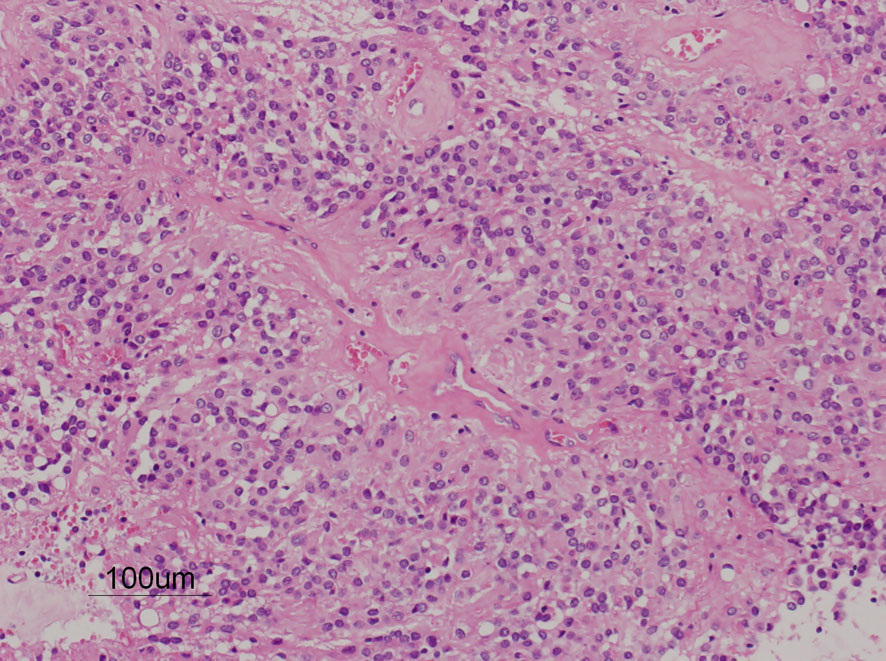

病理組織診断では退形成性上衣腫,MIB-1は40%以上にも達します。

摘出した標本のHE染色です。左側ではperivascular pseudorosette(血管周囲の無核野)がみられ,右側ではependymal tube (ependymal canal) が認められます。

グレード2の組織像です。血管周囲に無核野があり,腫瘍の核は血管から離れているパターンが特長です。perivascular pseudo-rosetteといいます。